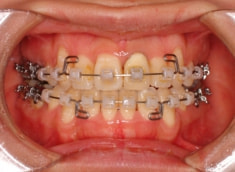

治療後(2年3ヶ月後)

治療開始から約1年後

歯根のパラレリング(平行性)が獲得されております。